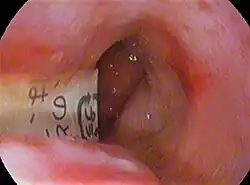

Foreign body in esophagus

Disk batteries, also called button cells, are often mistakenly ingested, particularly by children and the elderly. They may be mistaken for a medication pill because of their size and shape, or they may be swallowed after being held in the mouth while the battery is being changed. Battery ingestion can cause medical problems including blocked airway, vomiting, irritability, persistent drooling, and rash (due to nickel metal allergy).[4]